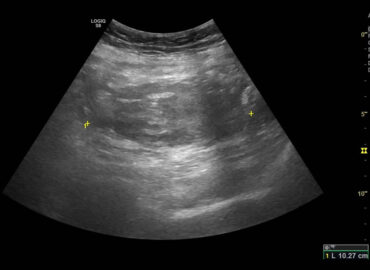

Paciente masculino de 25 años, sano previo, con dolor abdominal